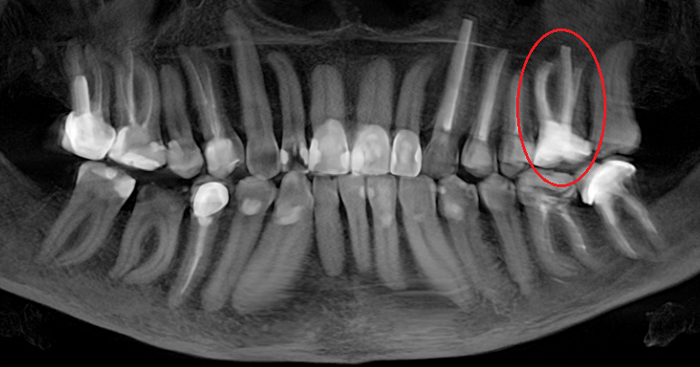

Согласитесь, не особо эстетично. Ортопантомограмма:

Фрагмент компьютерной томографии (вид сбоку):